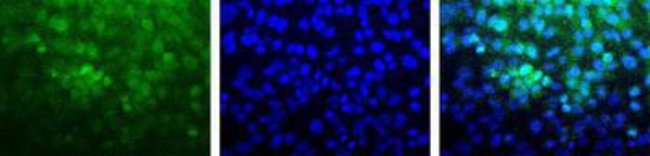

Tumor Growth Antibody Pack, For Research applications, Each

| Manufacturer Part Number | NBP178956 |